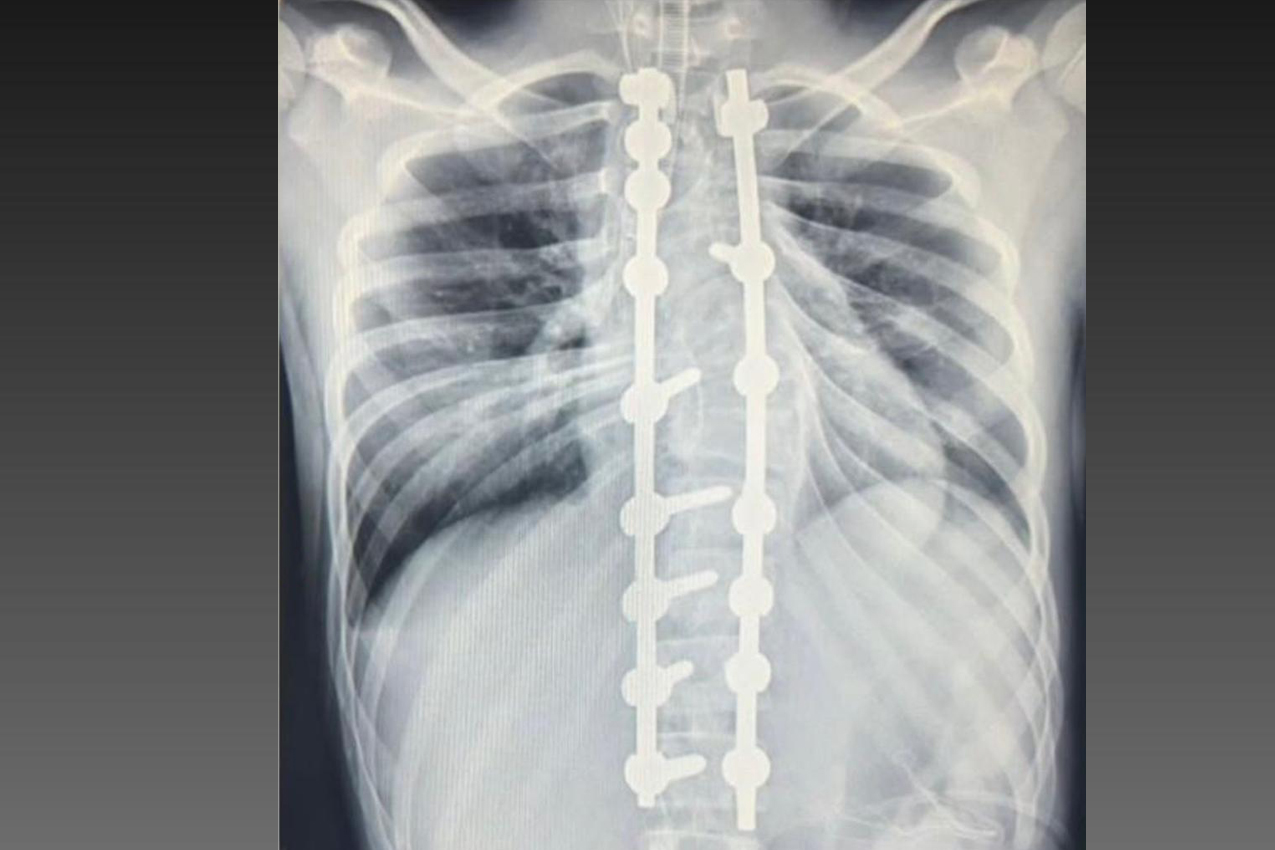

Laura era portadora de escoliose e, em agosto de 2025, realizou a cirurgia de correção da coluna, o que lhe permitirá ter uma vida normal de agora em diante. Moradora de Bom Sucesso do Sul, região Oeste do Paraná, é acostumada a andar a cavalo, mas com o problema na coluna a prática estava longe de ser prazerosa.

A cirurgia ocorreu no dia 28 de julho e uma segunda etapa em quatro de agosto. Desde então, Joyce viu a sua vida mudar. “Nasci com a escoliose e tinha muita dificuldade e limitações para caminhar e perda de movimento. Havia dias em que eu não levantava da cama. Quando saia de casa recebia olhares de julgamento das pessoas, que era o que mais me incomodava. Depois da cirurgia, posso dizer que eu tenho uma nova vida. Eu venci a batalha”, relatou.